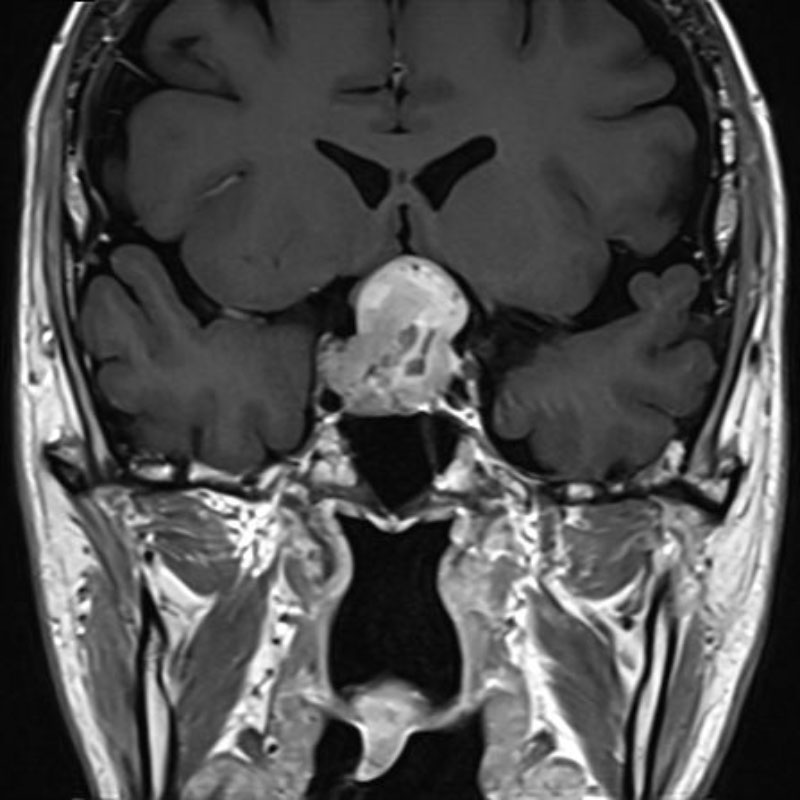

No.’25_113 手術前1

No.’25_113 手術前2